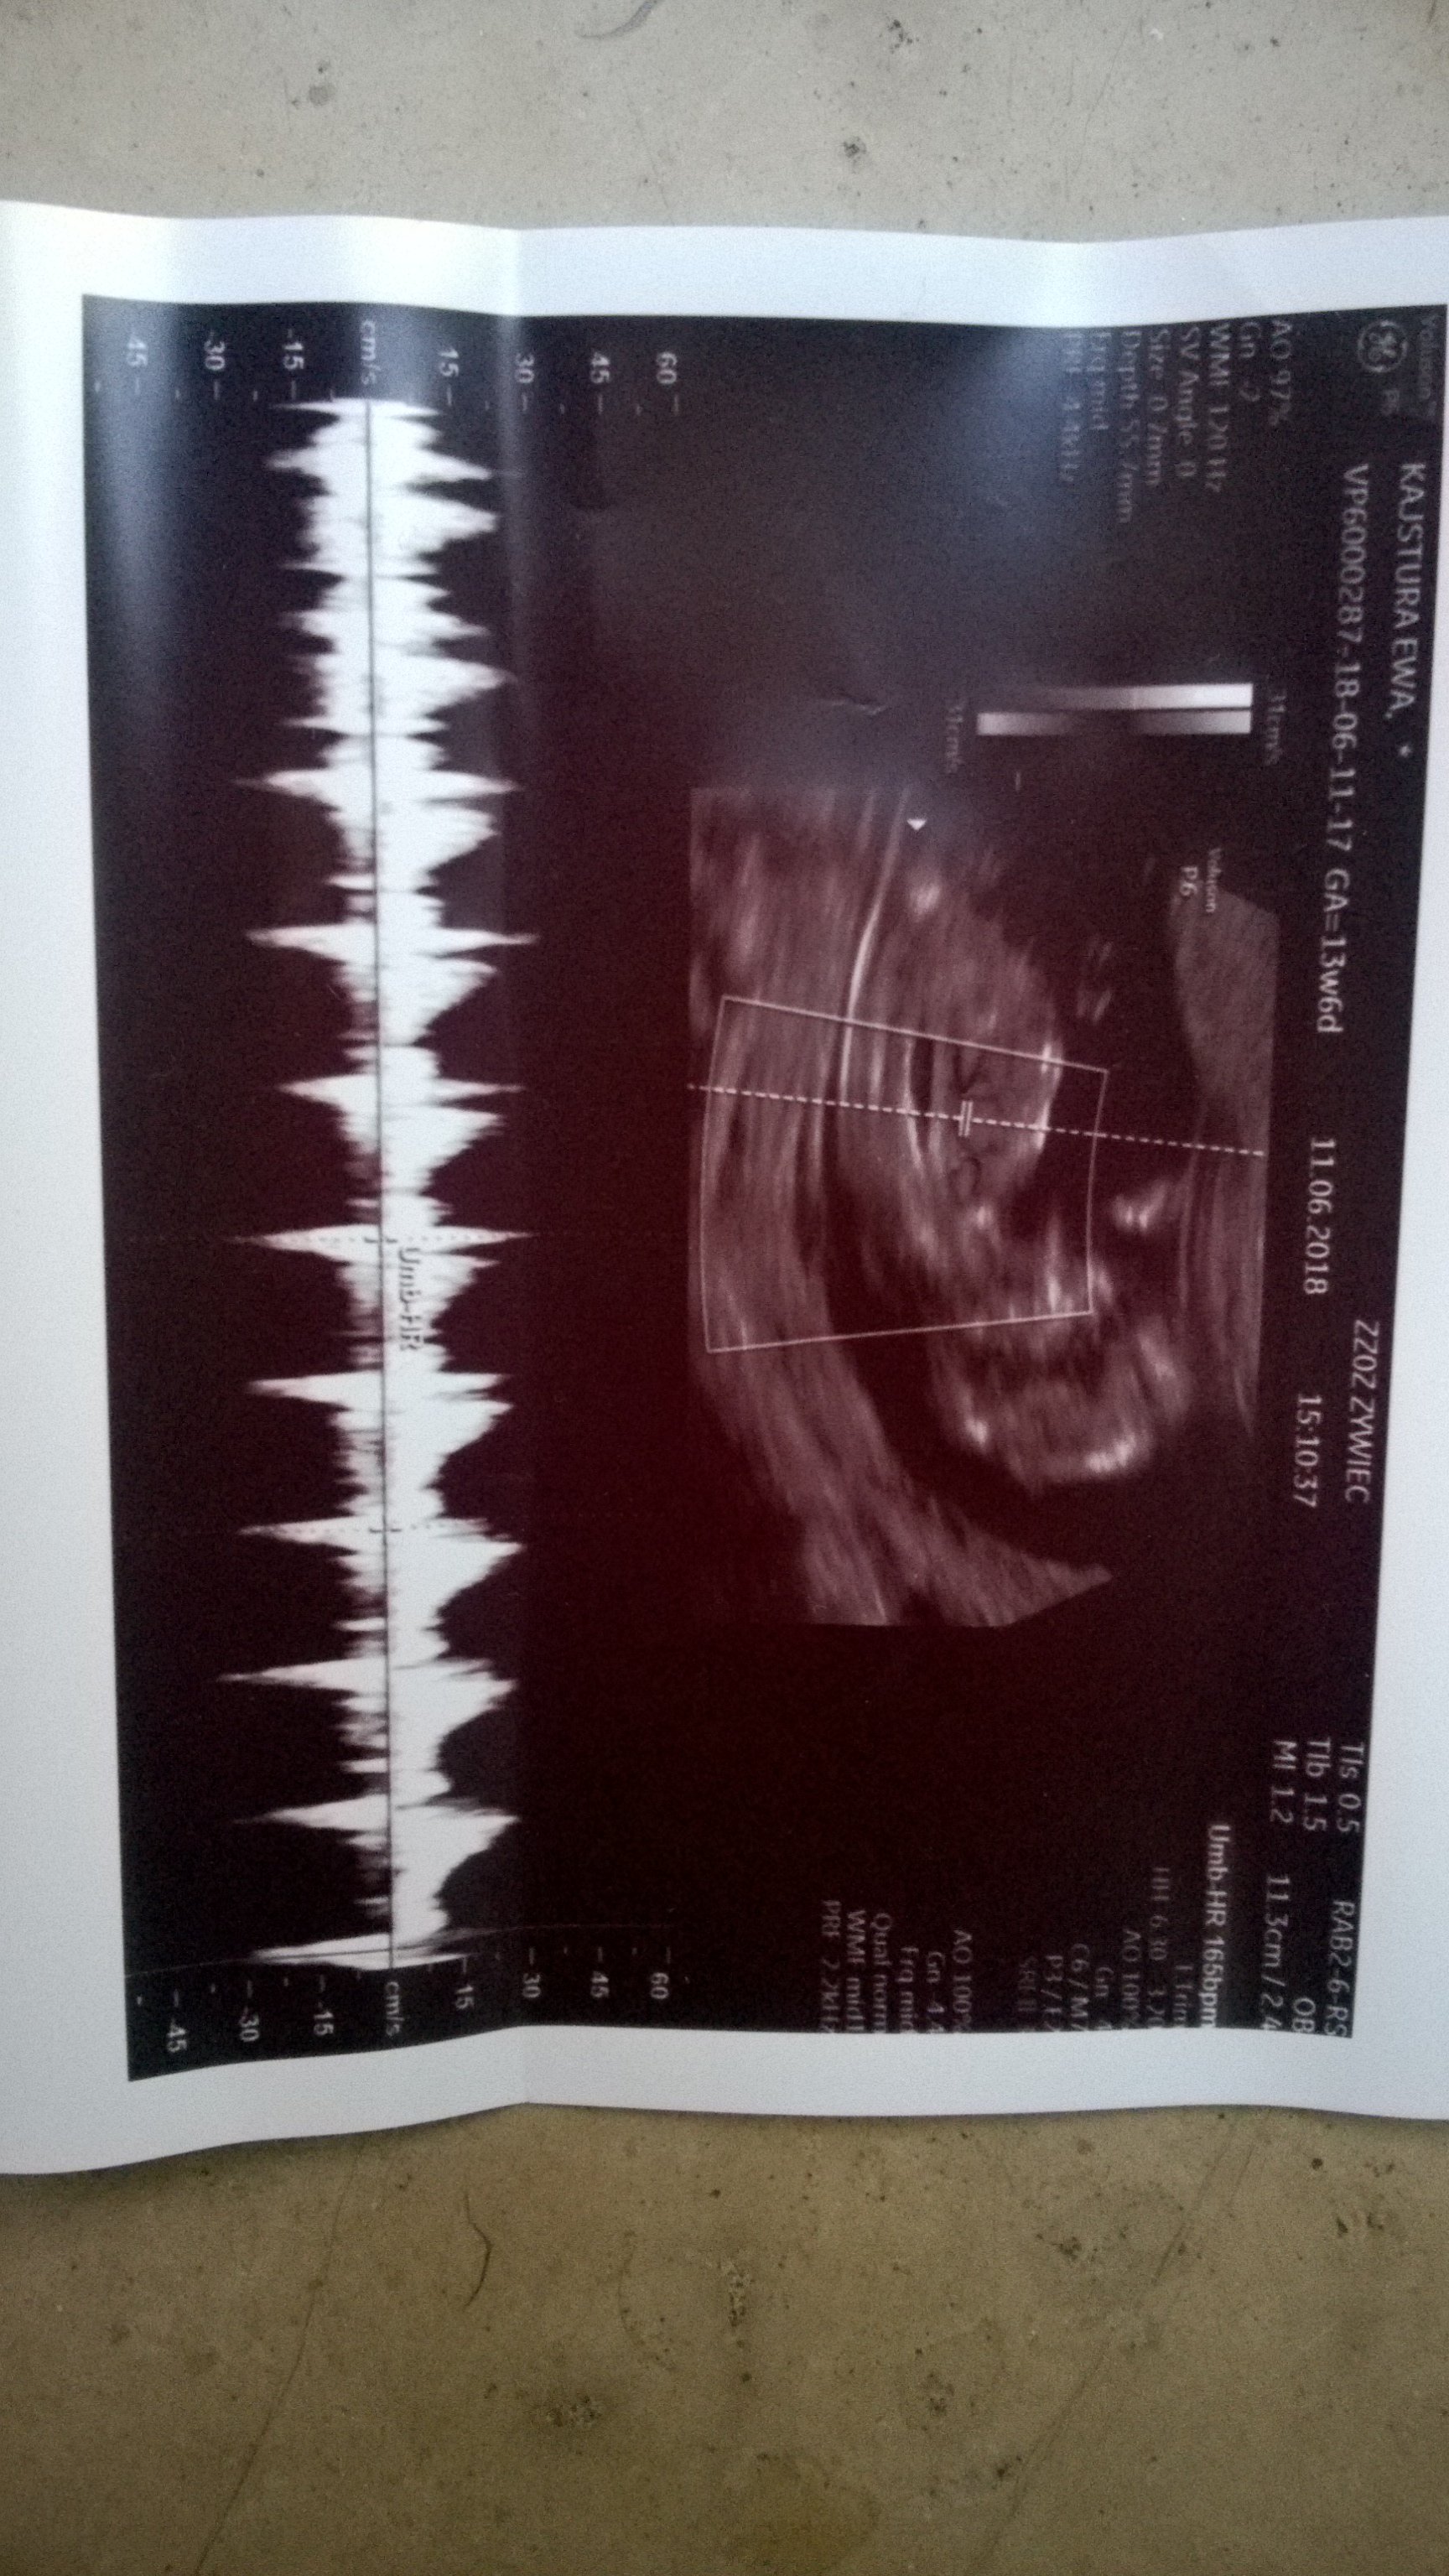

Serduszko pieknie mi bije..

Mama twierdzi, że będe jednak Remek

No i tyle sie dowiedzialam. Dostalam skierowanie na krew bo okazalo sie ze nie ma wszystkiego ☺

Kolejna wizyta 16 lipca ☺

Zobacz załącznik 866827